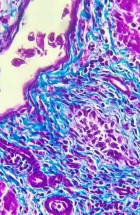

The Department’s main activities encompass research and specialized tasks. It focuses on clinical, pathoanatomical, pathohistological, immunohistochemical, and molecular diagnostics of diseases in both domestic and wild animals, including reproductive pathology. Operations within the department are structured around fieldwork and laboratory analyses.

- Performing pathohistological, cytological, immunohistochemical, and molecular diagnostics.